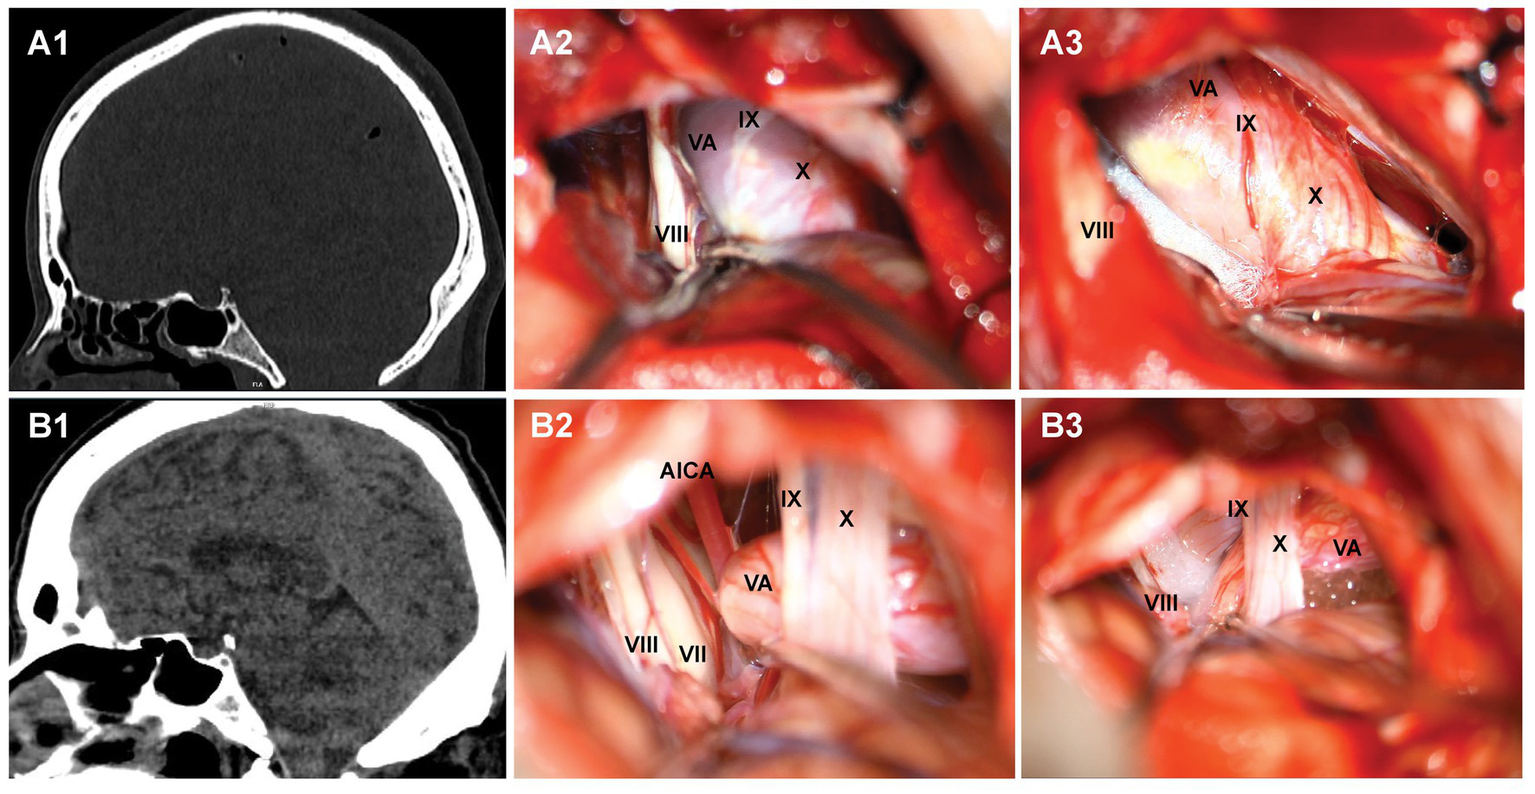

Figure 2

Two typical cases of hemifacial spasm. A1, B1: MPR post-processing after multi-slice spiral CT examination of the brain indicates that the posterior cranial fossa is narrow; A2, B2: exploration of the root of facial nerve in the cerebellopontine angle region revealed the compression of responsible vessels; A3, B3: placing padding cotton to separate the responsible blood vessels.